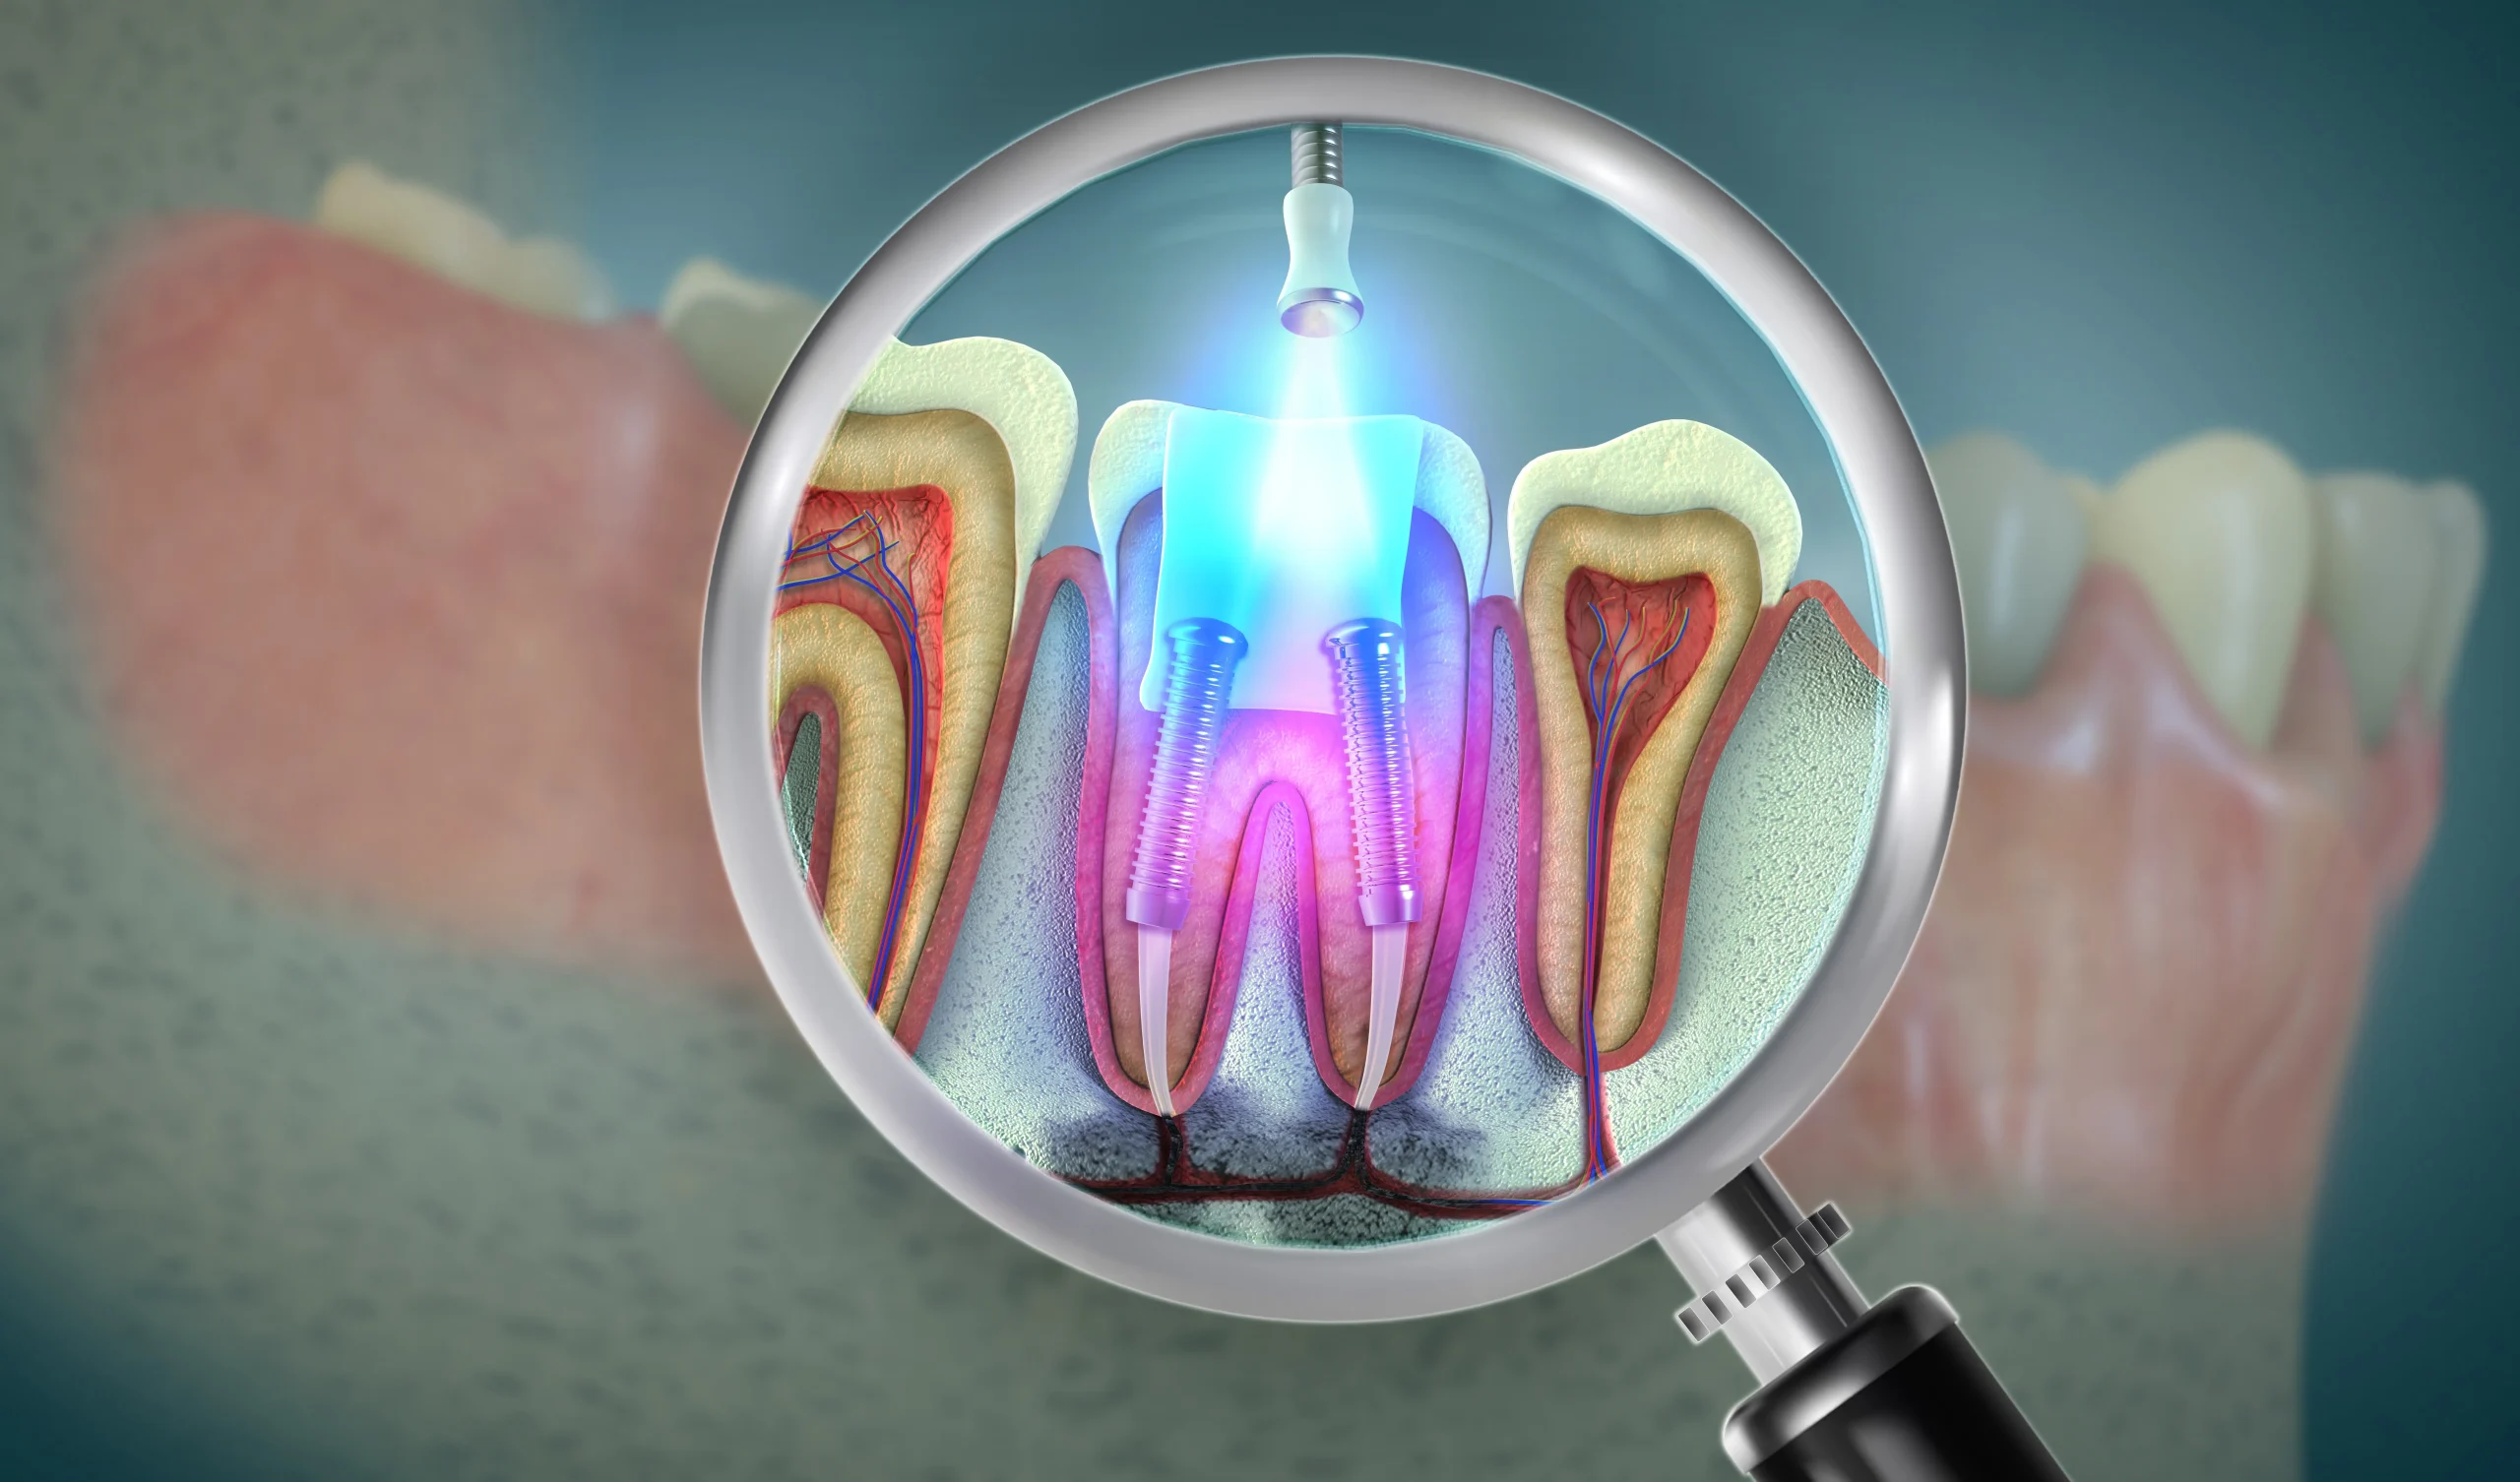

Digital X-rays help determine the exact depth of the canals, while rotary endodontic tools ensure precise cleaning and shaping. Once disinfected, the canals are tightly sealed to block bacteria. Finally, a crown reinforces the tooth for durability, restoring natural function and appearance.

Digital X-rays, apex locators, and rotary tools ensure highly precise treatment.

Digital X-rays, apex locators, and rotary endodontics ensure accurate, predictable, and long-lasting results.